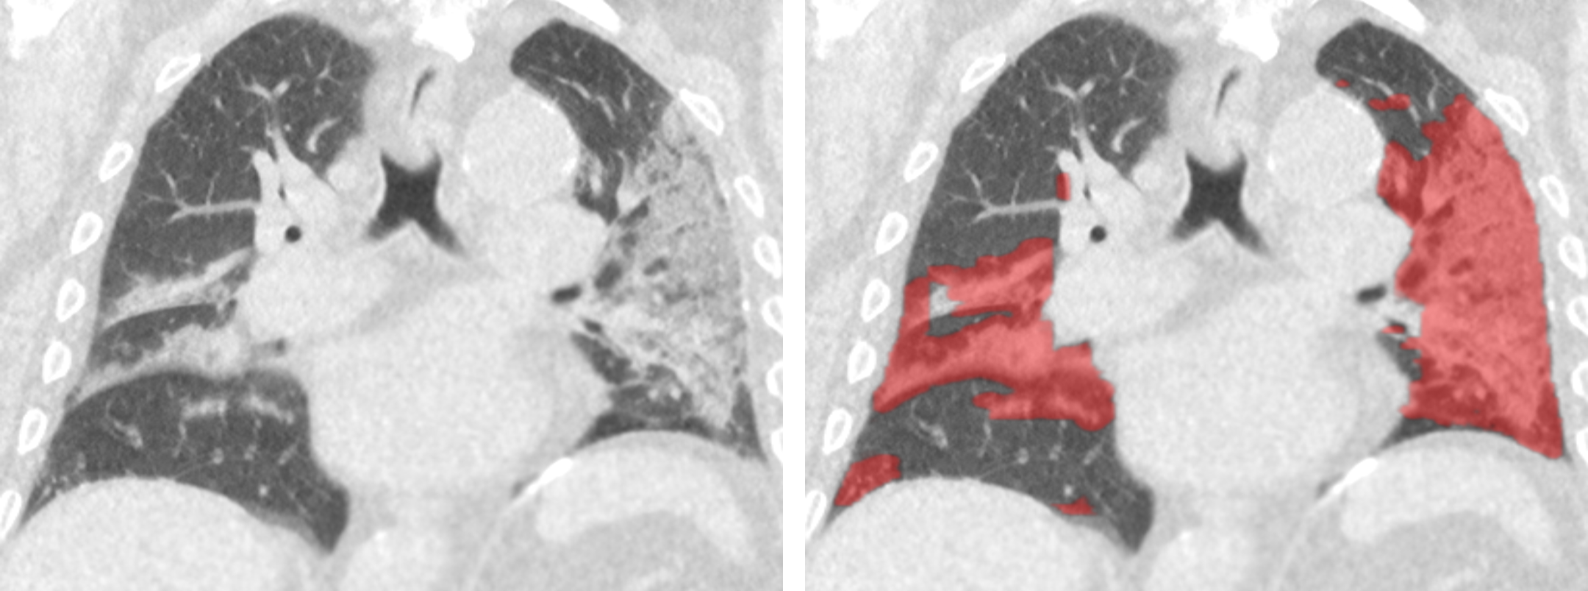

Na elke berekening komt er een pdf-rapport in het systeem te staan. Een radioloog bekijkt en beoordeelt alle rapporten over eventuele longschade. “Het rapport bevat een kwantificatie van hoeveel longweefsel is aangedaan in de verschillende longkwabben”, licht Lamb toe. “Daarnaast maakt het systeem een ‘overlay image’ aan, zodat de radioloog kan zien waarop het algoritme de keuze heeft gebaseerd.”